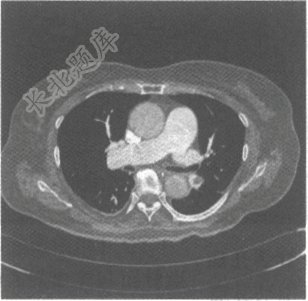

- 单项选择题男,39岁,突发胸痛,胸片未见异常,胸部增强CT如图。应诊断是

A、心肌梗死

B、肺动脉栓塞

C、肺结核

D、主动脉夹层

E、中央型肺癌